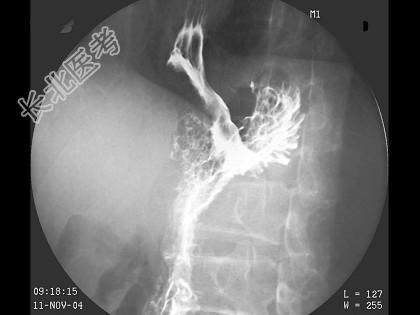

- 单项选择题男,59岁, 进行性吞咽困难半年,结合图像, 最可能的诊断为 ( )

D、食管癌

E、贲门癌侵及胃底、食管下段